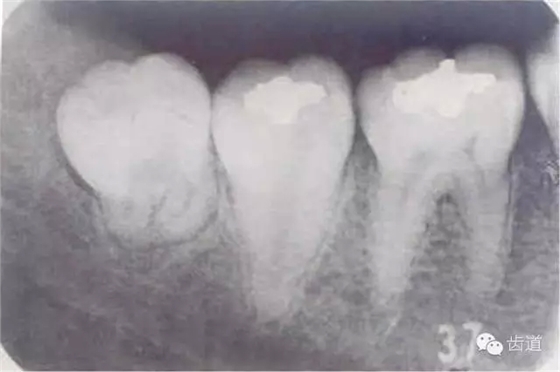

1、牙源性----最常見

1.人類進(jìn)化過程中,下頜骨體逐漸縮短,導(dǎo)致第三磨牙萌出空間不足,表現(xiàn)為部分萌出、牙位偏斜甚至完全埋伏阻生

2.冠周齦瓣形成盲袋,食物殘?jiān)M(jìn)入后不易清除,細(xì)菌在此生長繁殖

3.雙向受力,局部血運(yùn)差,細(xì)菌入侵

4.全身抵抗力下降時,急性發(fā)作